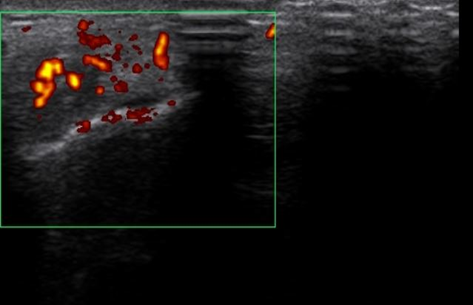

On retrouve à l’examen clinique une douleur à la palpation et à l’étirement au niveau de la partie latérale du coude gauche. Une échographie est réalisée à notre centre montrant : une déchirure partielle du tendon commun des extenseurs.

Coupe transverse du tendon commun des extenseurs démontrant la présence d’une hyperémie ( inflammation) au doppler puissance